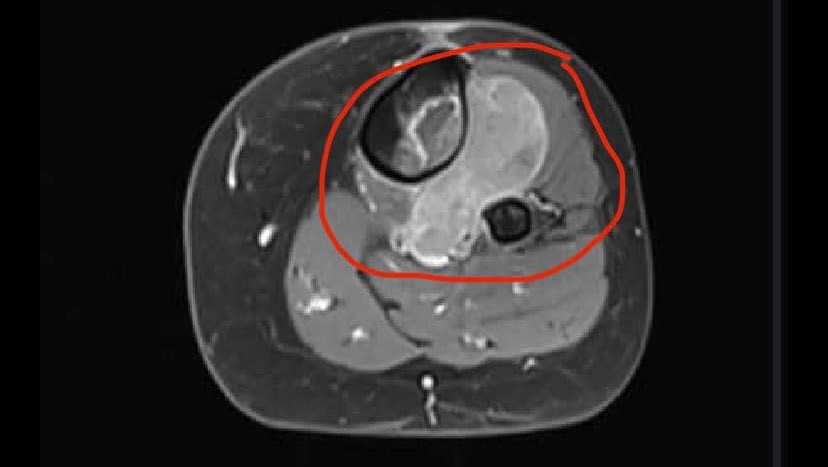

Life definitely changed very quickly for this new family back in Sept/Oct 2023 - a diagnosis of Ewings Sarcoma (rare aggressive bone cancer) in the left lower leg while also being only 3.5 months postpartum to our first baby - we were stunned nonetheless.

Surgery to remove the tumourous bone was scheduled between rounds 6 and 7 but scans revealed that while chemo was having a good affect on the cancer, the tumour had not receded back into the bone and away from the nerves and vessels enough. So no rest for the wicked! We continued on with our fortnightly chemo schedule with no break.